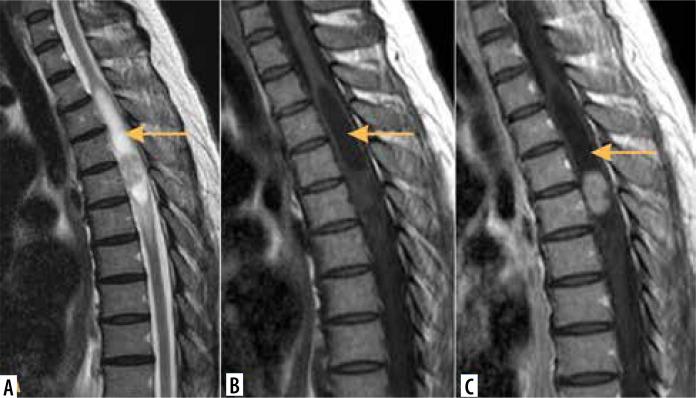

脊髓髓内肿瘤的影像学检查

Imaging of intramedullary tumours of the spinal cord.

Intramedullary tumours (IMTs) are the least common neoplasms of the spinal canal. The majority of them are ependymomas and astrocytomas, the third commonest is haemangioblastoma, while other tumours of the spinal cord are relatively rare. This review presents on update on the imaging of spinal cord tumours. Magnetic resonance imaging (MRI) is the imaging method of choice in diagnosing IMTs, with other modalities playing a supplementary role. The authors discuss the MRI protocol in IMTs including advanced techniques and present the imaging features of particular tumours. The differentiation of IMTs from other spinal cord diseases is also presented.

摘要

髓内肿瘤(IMTs)是椎管内最不常见的肿瘤。其中大多数是室管膜瘤和星形细胞瘤,第三常见的是血管母细胞瘤,而脊髓的其他肿瘤相对少见。本综述介绍了脊髓肿瘤成像的最新情况。磁共振成像(MRI)是诊断IMTs的首选成像方法,其他方式起辅助作用。作者讨论了IMTs的MRI检查方案,包括先进技术,并介绍了特定肿瘤的成像特征。还介绍了IMTs与其他脊髓疾病的鉴别诊断。